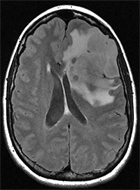

Clinique : femme de 31 ans, céphalées depuis 2 mois, parésie du membre supérieur droit.

Quel est votre diagnostic ?

Imagerie IRM conventionnelle :

Lésion frontale gauche cortico-sous-corticale, relativement bien limitée, en hypersignal FLAIR hétérogène avec petites zones nécrotico-kystiques en profondeur. Œdème périlésionnel modéré, mais effet de masse tumoral notable sur les sillons adjacents et la ligne médiane.

La masse est hypointense en T1. Prise de contraste nette, hétérogène, prédominante en zone profonde après injection